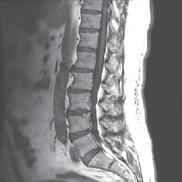

Positioning MIITT within radiology rather than the biomedical or electrical engineering departments kept the scientists both mentally and physically close to the end users.

“Our field of research takes place at the intersection of medicine and engineering,” says Principal Investigator, Gastao Lima da Cruz, PhD. One of the many benefits of the MIITT translational research group is in open collaboration between clinicians and engineers. Six medical doctors with MIITT primary affiliations are in active collaboration with the research scientists, postdoctoral fellows and graduate students. Working side by side in the Medical Science I building, investigators gain an understanding of real world clinical problems, then work together to solve them utilizing technology.

“This is a good example of a problem I’m having clinically that’s being solved by our research group,” says radiologist and scientist, Shane Wells, MD, Associate Professor of Radiology and Urology whose research focuses on improving diagnostic information to help urologists make more informed decisions. “I currently use ultrasound or CT to put needles into the liver to treat tumors. The needles get hot at the end and burn the tumor. It’s a minimally invasive procedure that can actually cure liver cancer and patients can go home the same day. However, one of the shortcomings of the current technology is that we can’t target tumors very well, which negatively affects patient outcomes. Now, the platform that we’ve developed at MIITT combines ultrasound and MRI to improve that tumor targeting.”

“One solution that we found is to use our Siemens MAGNETOM Free.Max 0.55T MRI Scanner,” says Dr. Seiberlich. As one of the few locations nationwide that owns and operates this “low field” machine, the MIITT team and UM Radiology have identified niche utilities, including the ability to conduct “in bore” biopsies--meaning the patient stays in the MRI scanner throughout the procedure. Now radiologists can clearly see the area that they want to biopsy, and accurately direct metallic needles without risk of damaging surrounding tissue. In addition to a wider bore, initially intended for larger patients or those with claustrophobia, the image quality of the scans is less affected by metal implants at low field strength. This is also advantageous when scanning patients with prior joint replacement surgery. “We can also capture MRI scans of parts of the body that are in motion, such as the heartbeat or blood flow,” she says. “Instead of a one second scan to make an image of a stationary body part, we can create a usable image in 20 milliseconds. We continue to discover special use cases that make this machine an exciting tool for us to have in radiology.”